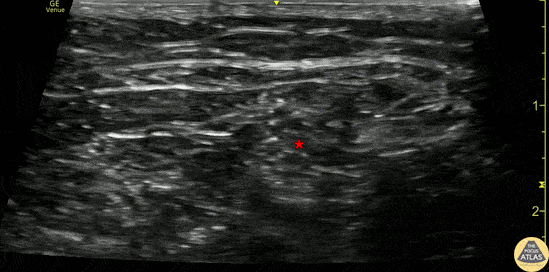

30s M presented with foot pain after an accidental injury from a lawn mower blade. Found to have a large laceration and open metatarsal fracture. A popliteal sciatic nerve block was performed for pain control overnight while the patient awaited surgery the next morning. The block is shown here, with the needle entering from the lateral aspect (right of screen), injecting anesthetic adjacent to the sciatic nerve (*) in the popliteal fossa. The patient had improved pain control and was admitted for surgery. Megan Foy, MS4, University of Colorado School of Medicine Dr. Adam Esch, PGY4, Denver Health Residency in Emergency Medicine